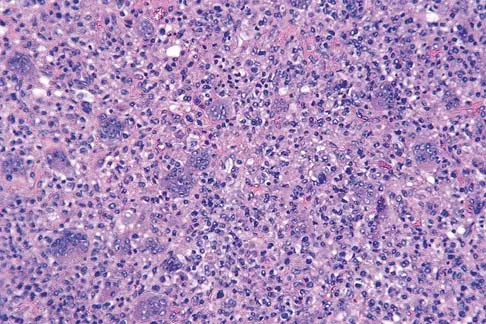

A 43-year-old woman is referred after excisional biopsy of a cutaneous soft-tissue mass from her left shoulder. Based on the biopsy specimens shown in Figures 44a and 44b, what is the best course of action?